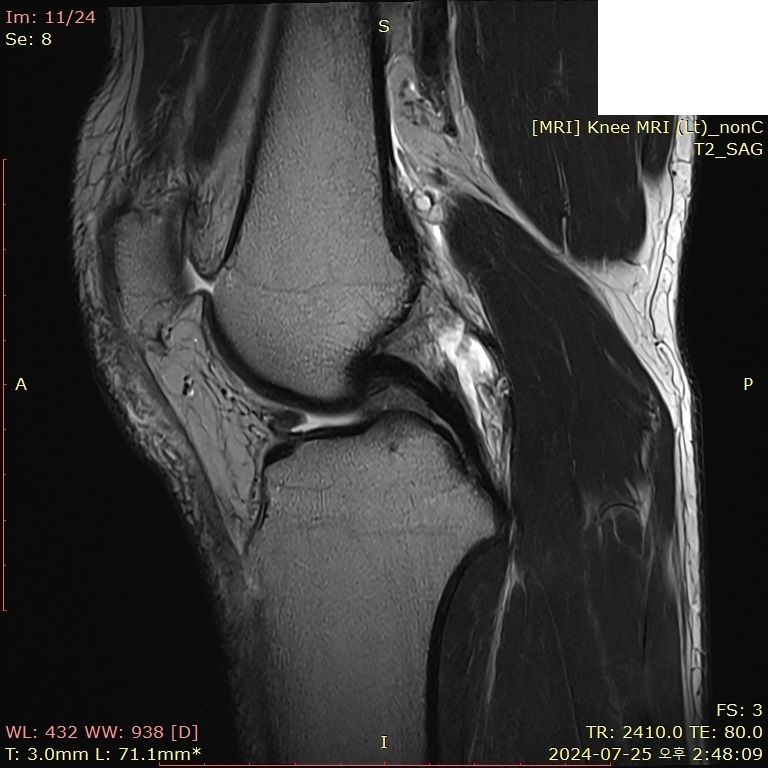

무릎 부딪혔는데 mri 한번 봐주시면 감사하겠습니다..

뛰다가 넘어졌습니다.. 예전에는 무릎이 부어도 병원 안 갔는데, 최근에는 중요성을 알아서 미리미리 검진 받자는 의미로 갔다왔습니다

• 3번 째 사진

보여주신 MRI만 보면 전방, 후방 십자인대 손상이 의심되지 않습니다.